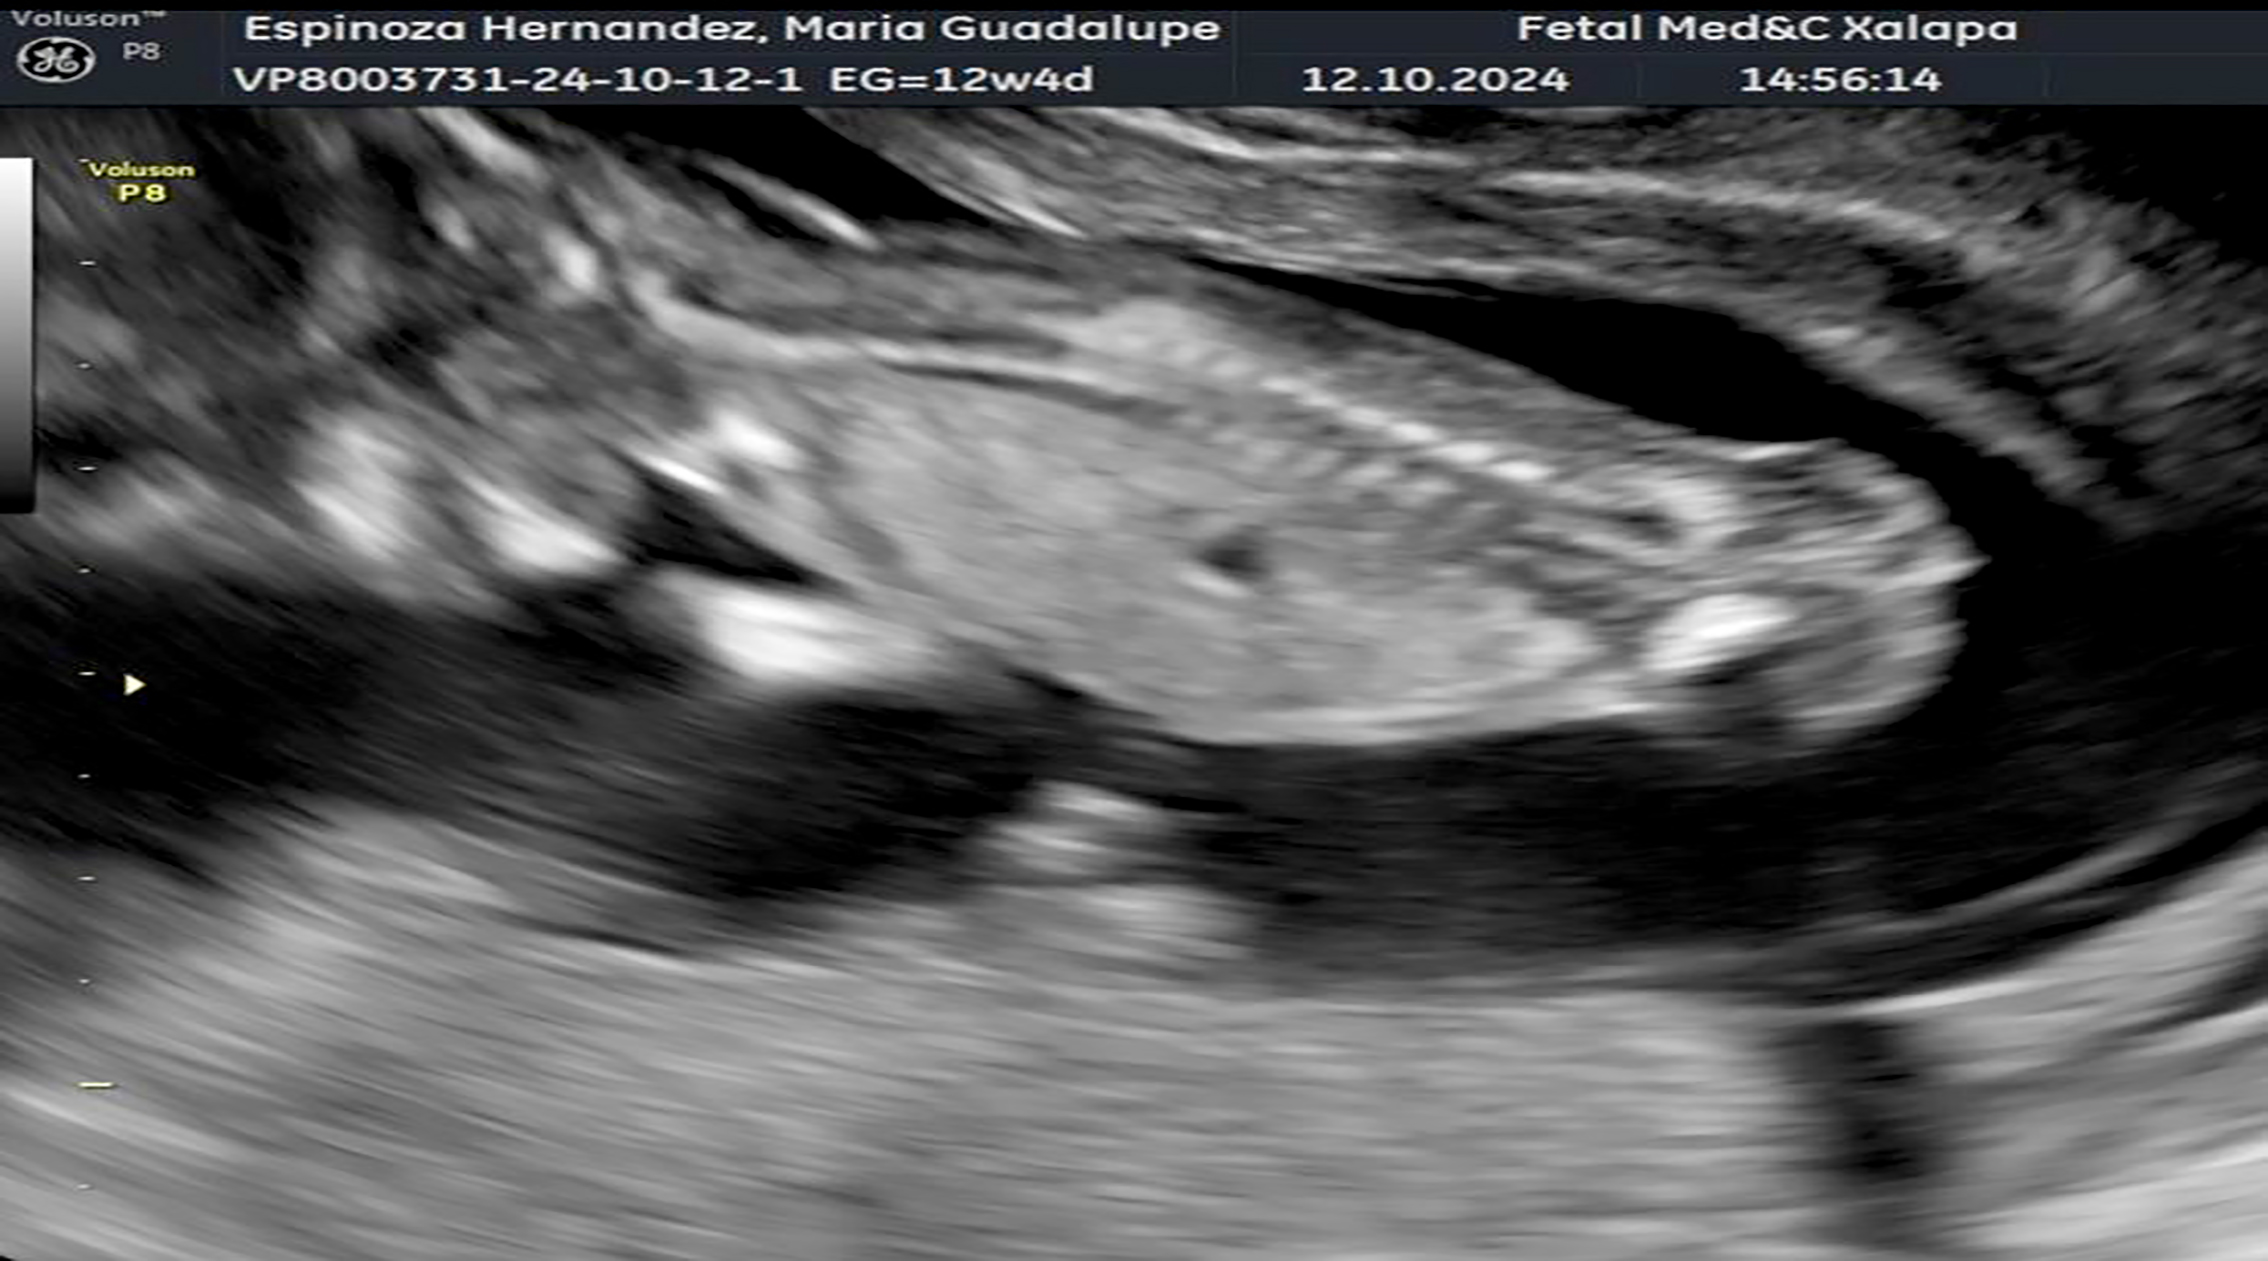

• Radiografía del bebé de la señora María Guadalupe Espinoza, a quién se le realizó la primer cirugía fetal en el estado dentro del Centro de Alta Especialidad (CAE), por una malformación que se le detectó, resultando con éxito. Foto Secretaría de Salud.